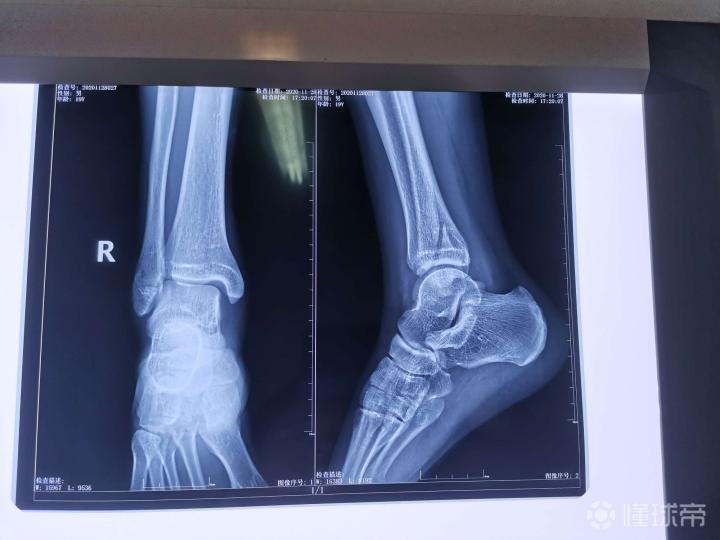

远端腓骨骨折 错位 明天手术 打钢板 懂球帝